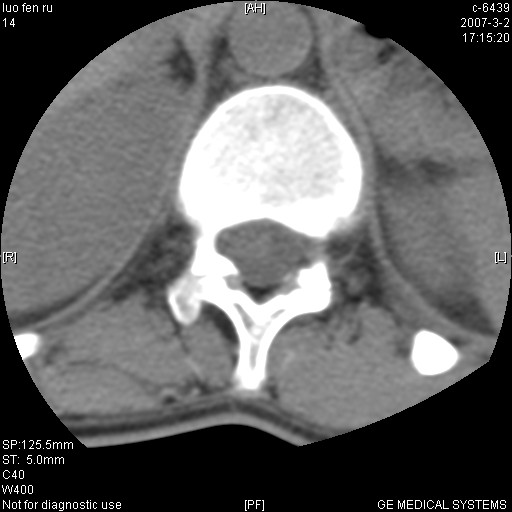

标题: CT6952:T11椎体病变请讨论

女,19岁.背部疼痛一月余.自诉幼时有个外伤史.

腰椎平片示,t11椎体呈楔形改变,椎间隙未见异常.

第一感觉就像嗜酸性肉芽肿,骨折及tb不能解释表现

1、陈旧性的骨折。2、嗜酸性肉芽肿。

t11椎体前缘不规则形骨质破坏,周围有硬化边,软组织肿块不明显,首先考虑:骨嗜酸性肉芽肿 。期待随访结果。